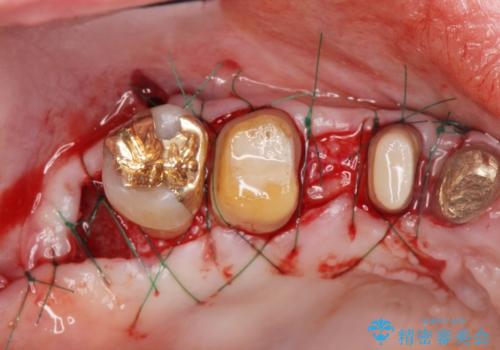

歯周ポケットの除去を併用したセラミック治療

適合や審美性に優れるセラミック治療を行う前に、歯周病の問題を歯周外科を行うことで解決し将来的に不安のないような口腔内環境を整備していきます。

- 110万円(ジルコニアクラウン×6・仮歯×6 歯周外科×2)費用は治療当時の料金となります

治療前に4-5mm程度あった歯周ポケットは全て2mm以内となり、非常に清掃性が高く、歯周病の再発しずらい環境に整えた上でのセラミック治療を実践することができました。